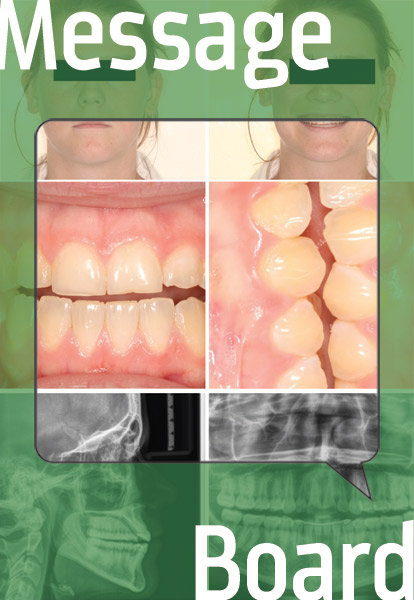

A 22-year-old female who finished treatment six years ago is having trouble biting into food. What would you do?